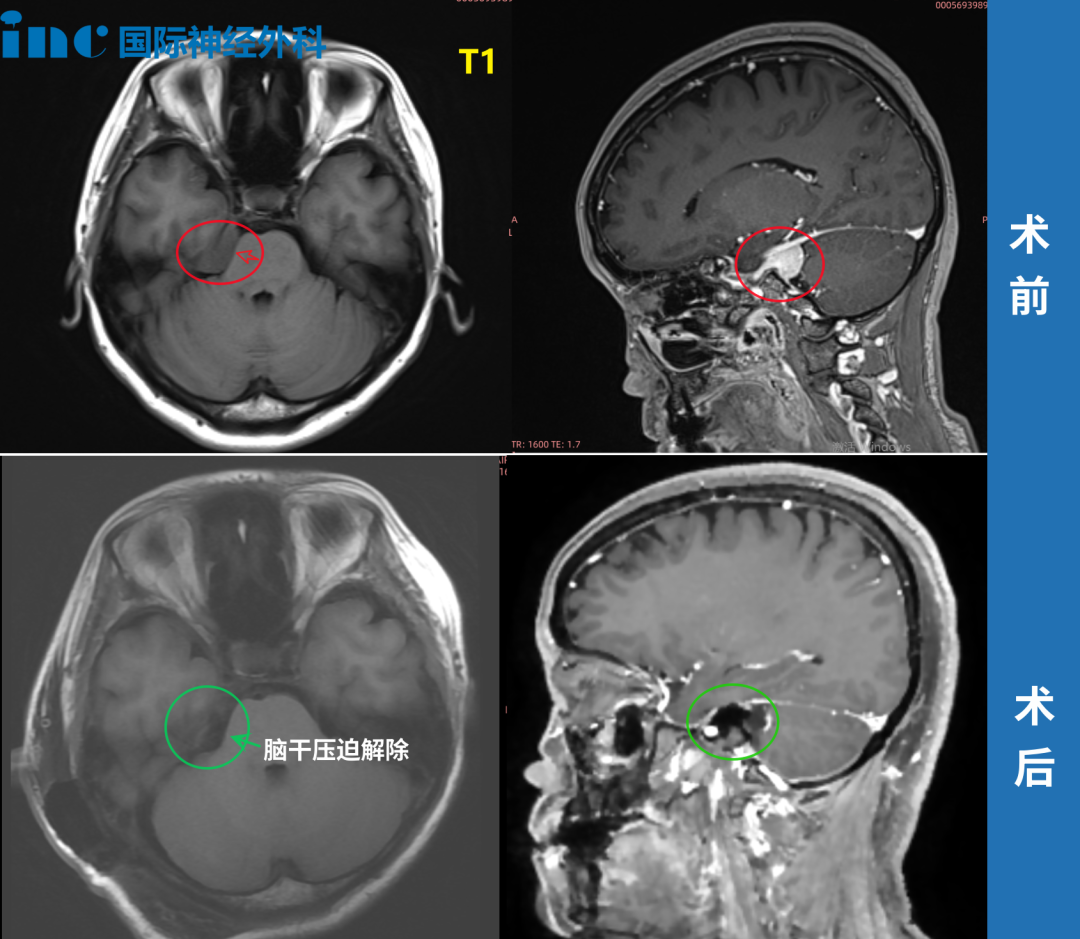

在北京天坛医院,INC福教授为她成功手术——“我在ICU里面呆了4个多小时就出来了,第2天下床,第9天出院。”点击阅读:天坛医院手术纪实|4.5cm脑膜瘤紧压脑干成功手术,勇敢辣妈的彪悍人生!

41岁的周女士同样在体检中发现桥小脑角(CPA)区脑膜瘤。肿瘤虽小,位置却极其棘手:与纤细的滑车神经、三叉神经紧紧粘连,同时还压迫桥脑和中脑——这是生命的中枢。她没有等到剧烈头痛或面瘫偏瘫出现,正是这份体检报告,让她在神经功能尚完好时抓住了治疗的“黄金窗口期”,最终由巴教授主刀完成高难度手术,及早解除风险。